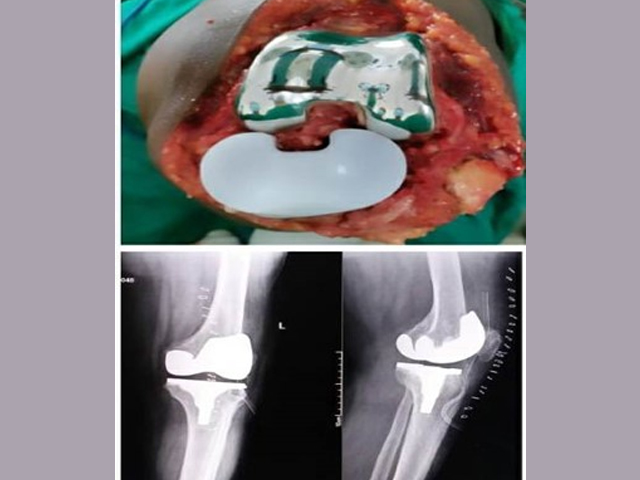

Joint Replacement:

We perform hip, knee replacement surgeries with high success rates. The department handles complex deformities and attracting referrals from across the district. Our surgeons use the latest technology and techniques to minimize post-operative complications and ensure rapid recovery.

Primary Hip, Knee,Shoulder and Elbow Arthroplasty